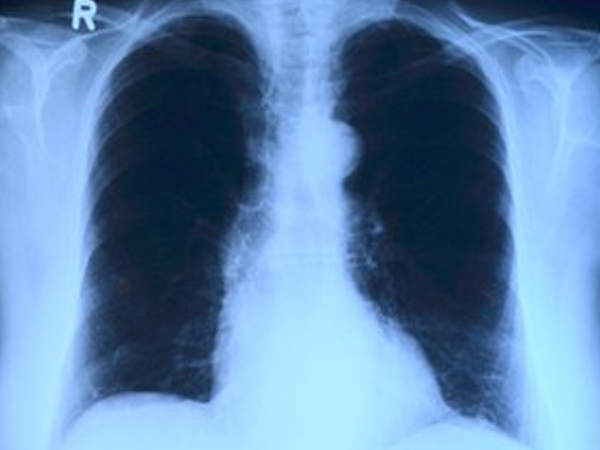

ద్రవం ఎక్కడ పేరుకుపోయిందో చూడటానికి తరచుగా X- రే లేదా EKG తీసుకోబడుతుంది. ఇది అకాల ఊపిరితిత్తుల క్యాన్సర్ సంభావ్యతను తొలగిస్తుంది.